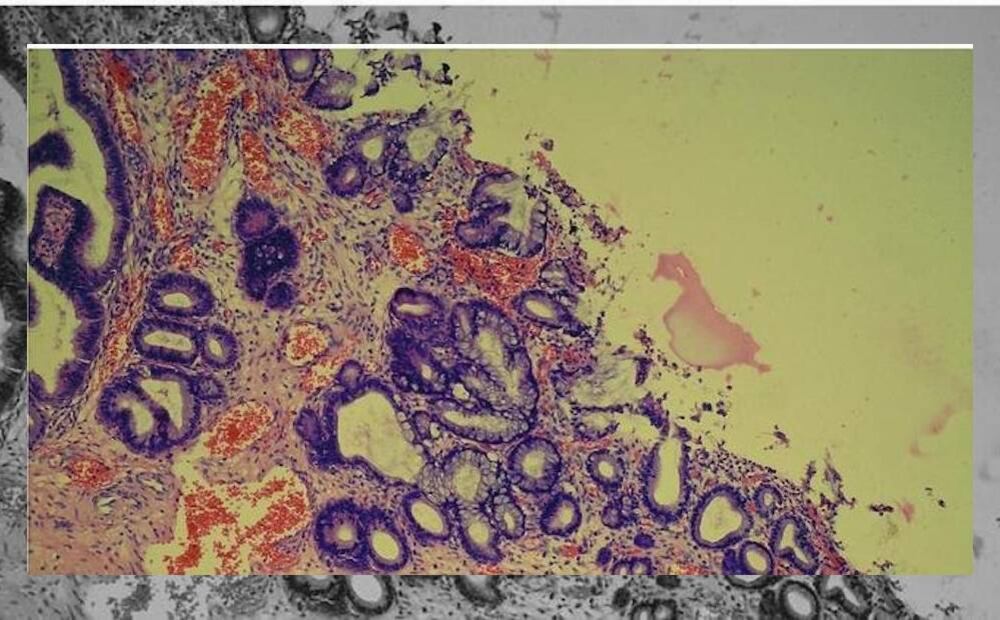

¿Qué es el VPH y cómo se transmite ?

El Virus del Papiloma Humano (VPH) es una enfermedad de transmisión sexual, que se transmite a través del contacto directo de piel durante el sexo vía vaginal, oral o anal.

De acuerdo con el sitio web de ‘Centros para el Control y la Prevención de Enfermedad’, el VPH puede transmitirse incluso si una persona infectada no presenta síntomas.

Los síntomas más comunes del virus pueden ser la aparición de verrugas genitales que aparecen en pequeños bultos o grupo de bultos en la zona genital alrededor del pene o ano.